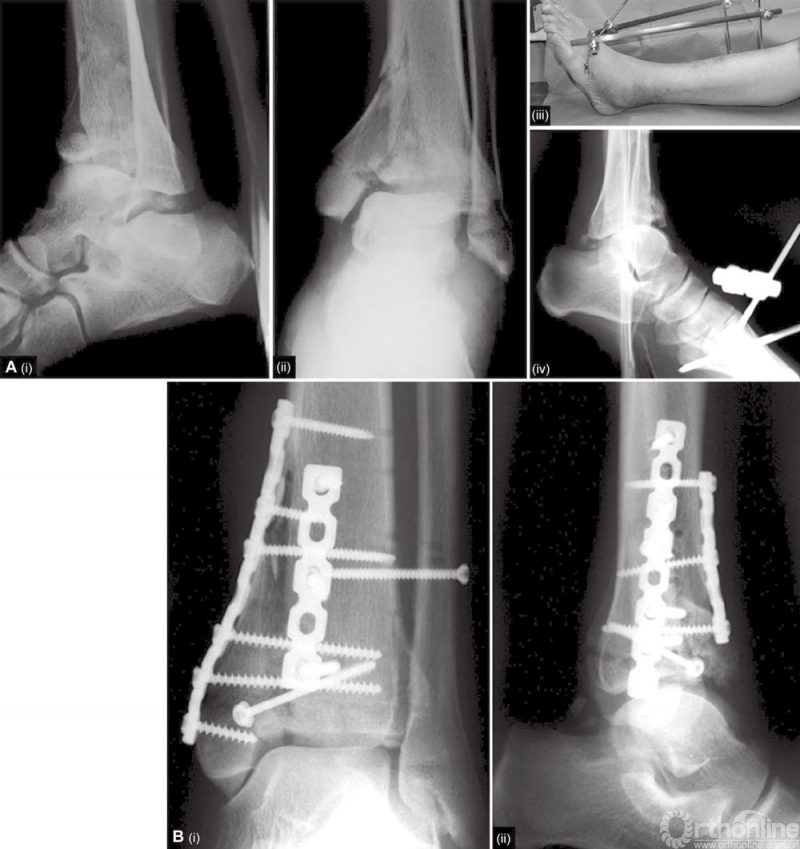

主要的软骨缺损必须要用骨移植物进行填充。移植骨的金标准仍然是来自髂嵴的自体骨移植。有时需要用皮质海绵骨移植支撑明显的骨缺损。钢板最终用来固定Pilon骨折。在Ⅰ、Ⅱ型骨折中,支撑钢板的轮廓贴合胫骨远端的内侧面就足够了。3.5 DCP或低切迹钢板放置到胫骨的内侧面(图8)。如果骨折向近端延伸,一个微创经皮固定技术在骨干是可行的。三叶接骨板覆盖骨面较大,可能会阻碍血运。

图8 A和B B型骨折用重建板和拉力螺钉进行固定